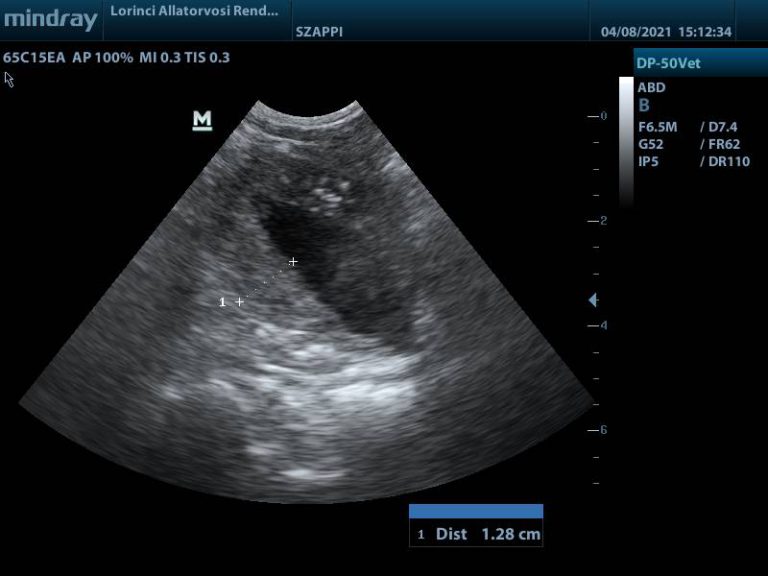

Húgyhólyag nagy részét kitöltő daganat

Megvastagodott hólyagfal és calcificatio

Bal vesemedence és urether tágulat

A hasi ultrahangvizsgálat során, telt hólyag mellett lehetőség van többek között a falszerkezet és falvastagság elbírálására. Az ép húgyhólyag fala kutyákban 3 mm-nél, macskákban 2 mm-nél nem vastagabb, sima felszínű, egyenletes. A falvastagságot kissé befolyásolja a hólyag teltsége, minél több vizelet van a hólyagban, annál jobban ellaposodik.

Ha a hólyag fala egyenetlen, megvastagodott, vagy massza türemkedik a hólyag üregébe – különösen a trigonum tájékán -, az aggodalomra adhat okot. Az ultrahang azonban önmagában nem különíti el a daganatos – és gyulladás miatti elváltozásokat, viszont a citológiával, illetve szövettani vizsgálattal együtt hasznos és fontos vizsgáló módszer.